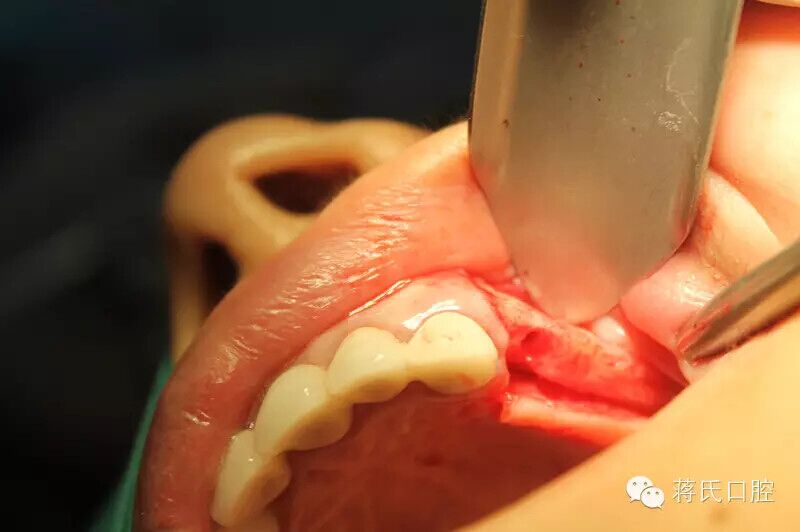

9.左側(cè)種植前口內(nèi)

10.左側(cè)切開(kāi)后

11.第一洞制備完成

12.左側(cè)外提升過(guò)程